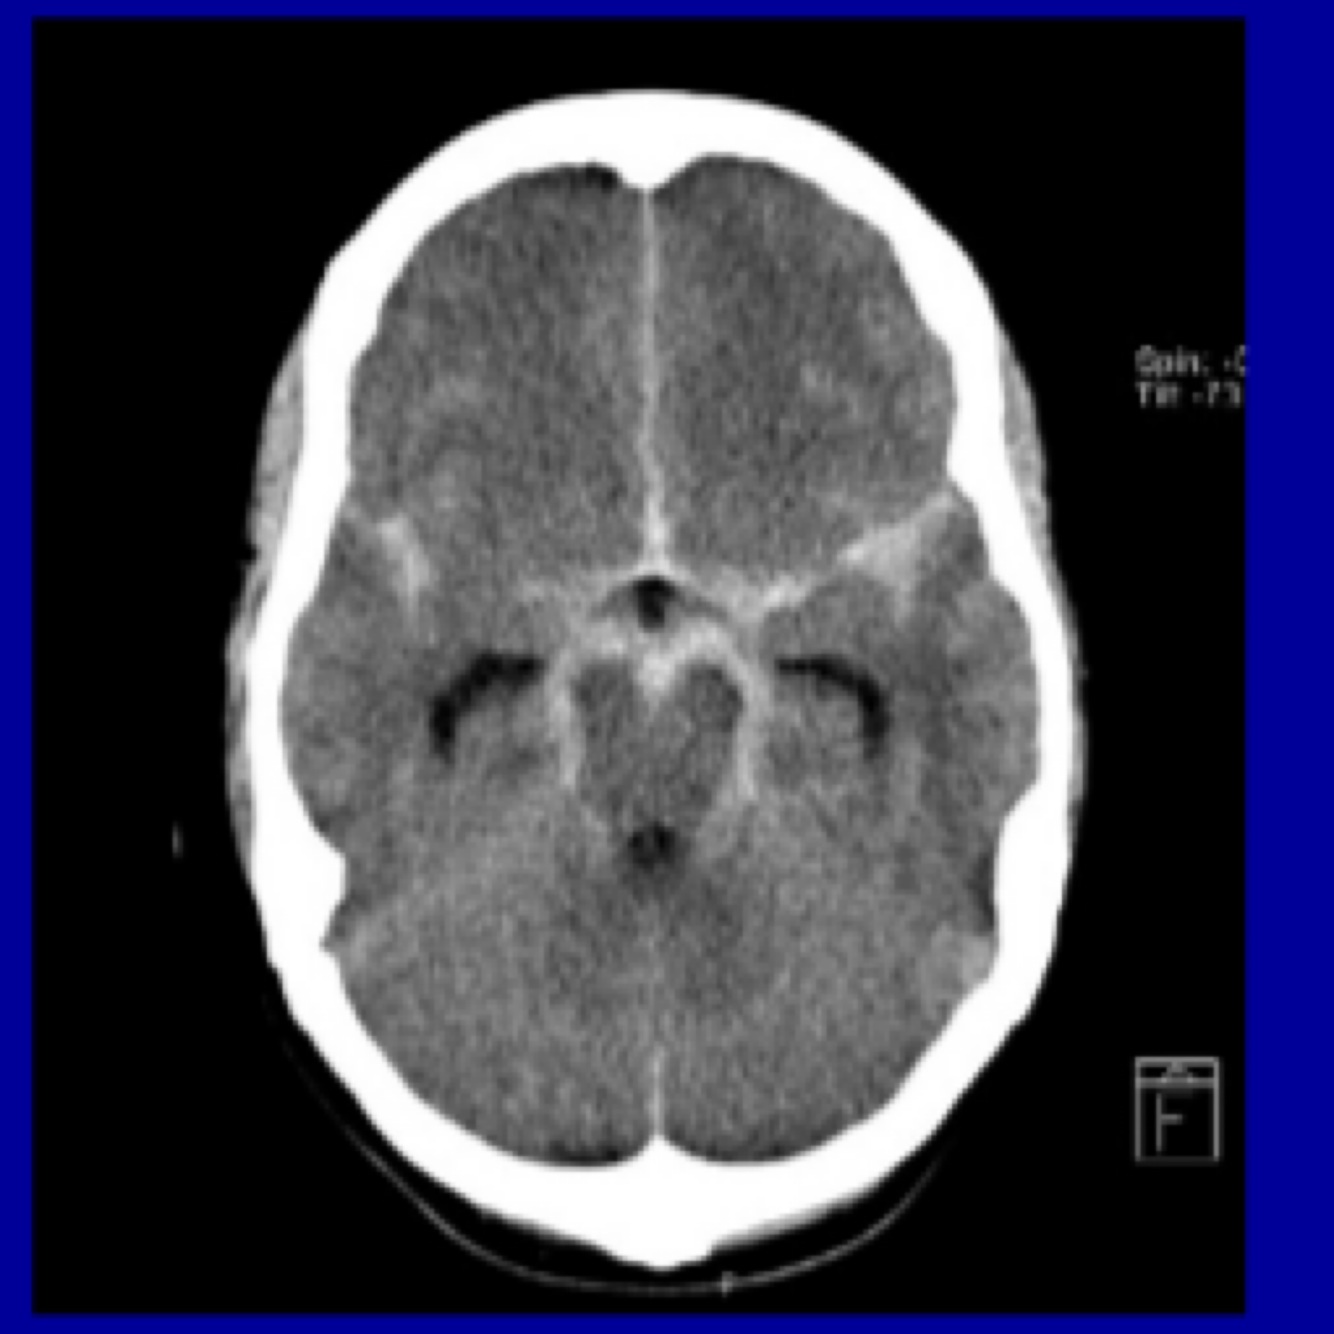

What is the investigation for SAH

CT head ASAP LP > 12hrs after headache onset CT angiogram if SAH confirmed